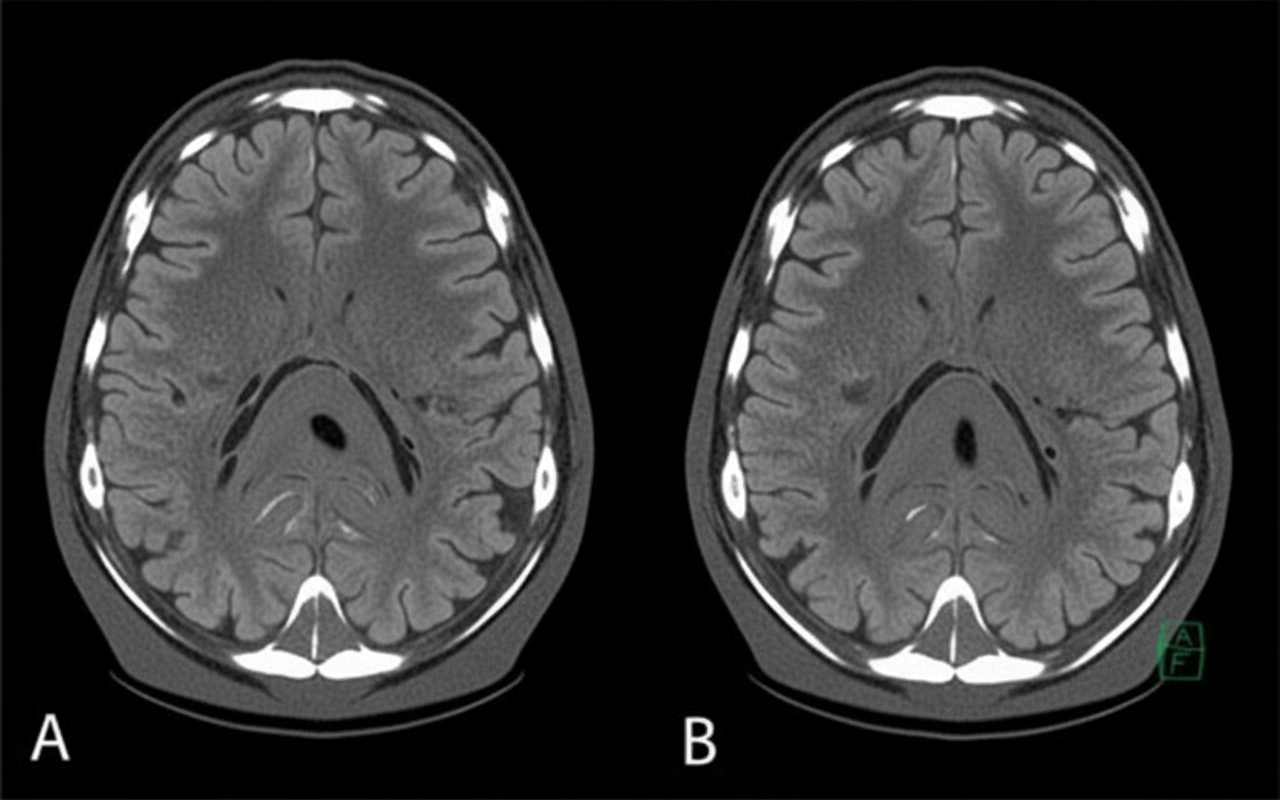

A 58-year-old man presents to the clinic concerned about his health after his elder brother recently became bed-bound due to a brain condition. He has also brought a head CT scan of his brother to reference, as shown in the picture. The patient has type 2 diabetes mellitus, hypertension, osteoarthritis, and hypercholesterolemia. His medication list includes aspirin, diclofenac sodium, metformin, and ramipril. He leads a sedentary lifestyle and smokes one pack of cigarettes daily. He also drinks 4–5 cups of red wine every weekend. His BMI is 33.2 kg/m2. His blood pressure is 164/96 mm Hg, the heart rate is 84/min, and the respiratory rate is 16/min. Which of the following interventions will be most beneficial for reducing the risk of developing the disease that his brother has?